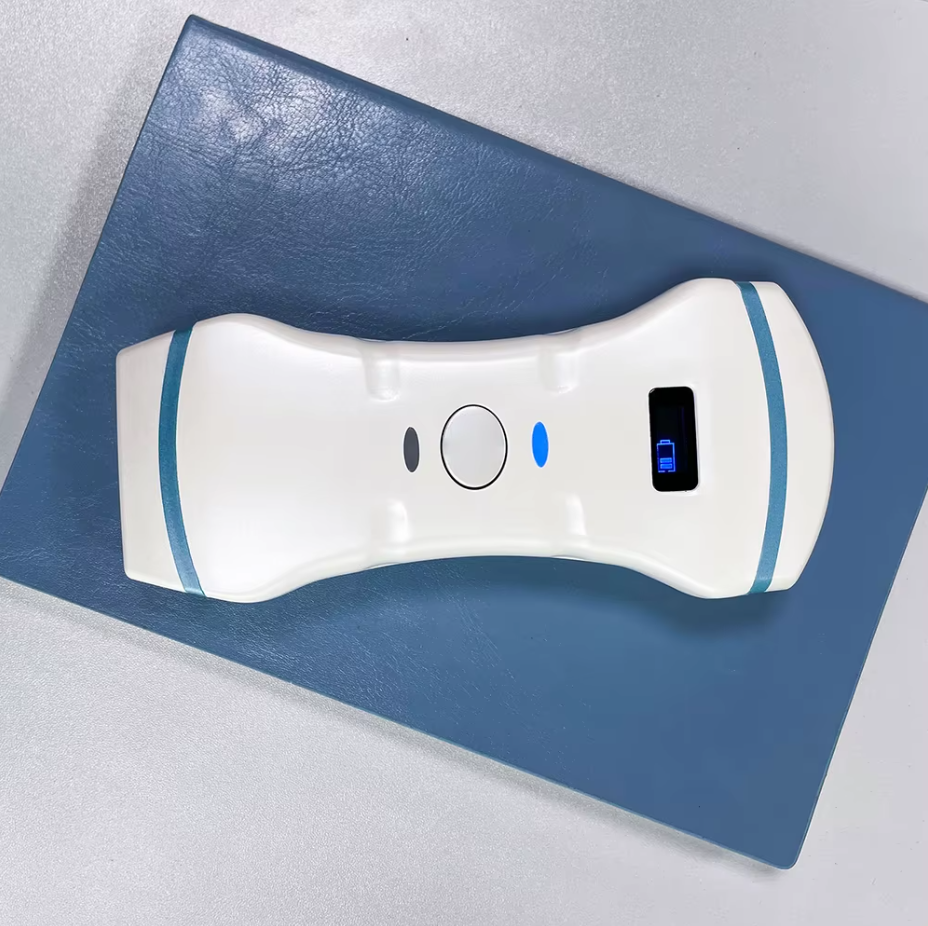

D5CL

El escáner de ultrasonido portátil de doble sonda es una solución avanzada diseñada para ofrecer máxima versatilidad clínica en un solo dispositivo. Gracias a su tecnología integrada, combina tres modos de escaneo —convexo, lineal y phased array— permitiendo evaluar estructuras profundas, tejidos superficiales y realizar estudios cardíacos con alta precisión. Esta integración reduce significativamente los costos al reemplazar la necesidad de adquirir múltiples sondas por separado.

Su diseño compacto y liviano lo convierte en una herramienta ideal para emergencias, rondas hospitalarias, clínicas comunitarias y evaluaciones en terreno. La conexión inalámbrica a tabletas o smartphones facilita su uso en quirófano sin cables, además de proporcionar una experiencia más cómoda y eficiente. Su funda protectora desechable permite una esterilización rápida y segura, mientras que su diseño impermeable mejora el control de infecciones.

| Dimensión | 156 x 60 x 20 mm |

| Peso | 250 gramos |

Elegante

- Pequeño, es práctico para sostener/escanear y guardar en un bolsillo.

156 x 60 x 20 mm

-

250 g